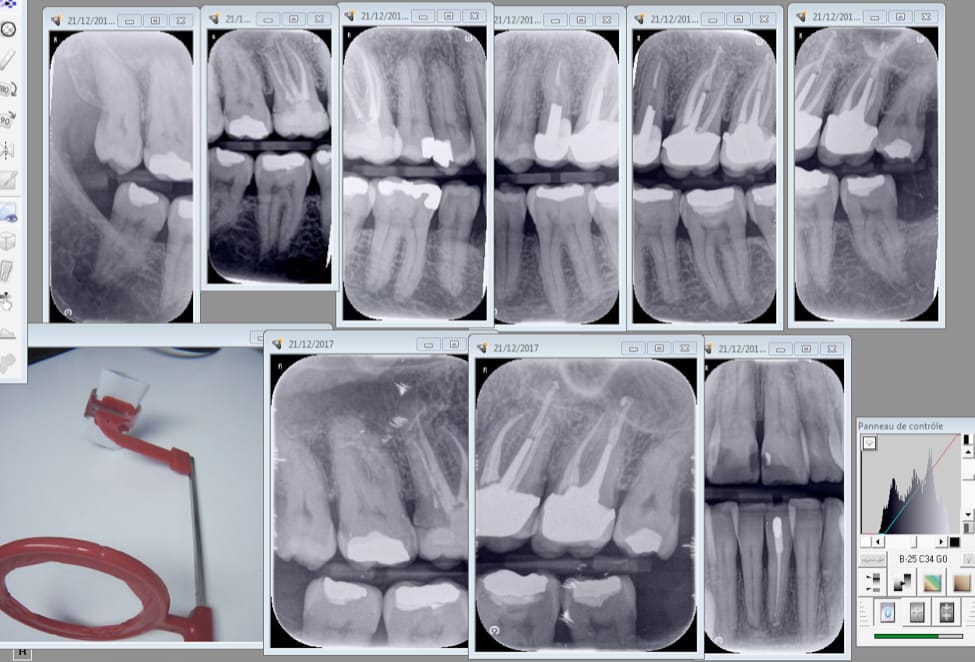

Capture d écran 2017 12 21 21.21 - Eugenol

Ba2be871 3220 4edb a5bc d126045cb763 jy2fsv - Eugenol

cyber ratiches

22/12/2017 à 08h04

Comment arrive tu à obtenir ces clichés ?

taille 3 vertical. Un seul angulateur qui fait tout avec tous les films droite gauche haut et bas en fonction de la position du film. . Dentsply pour capteur en rétro coronaires Vertical à la base. Ergonomie ++++

Capture d écran 2017 12 22 09.07 - Eugenol

chicot29

22/12/2017 à 09h18

Haut et bas sans modifier l'angulateur. Seulement la position du film. Ici taille 2.